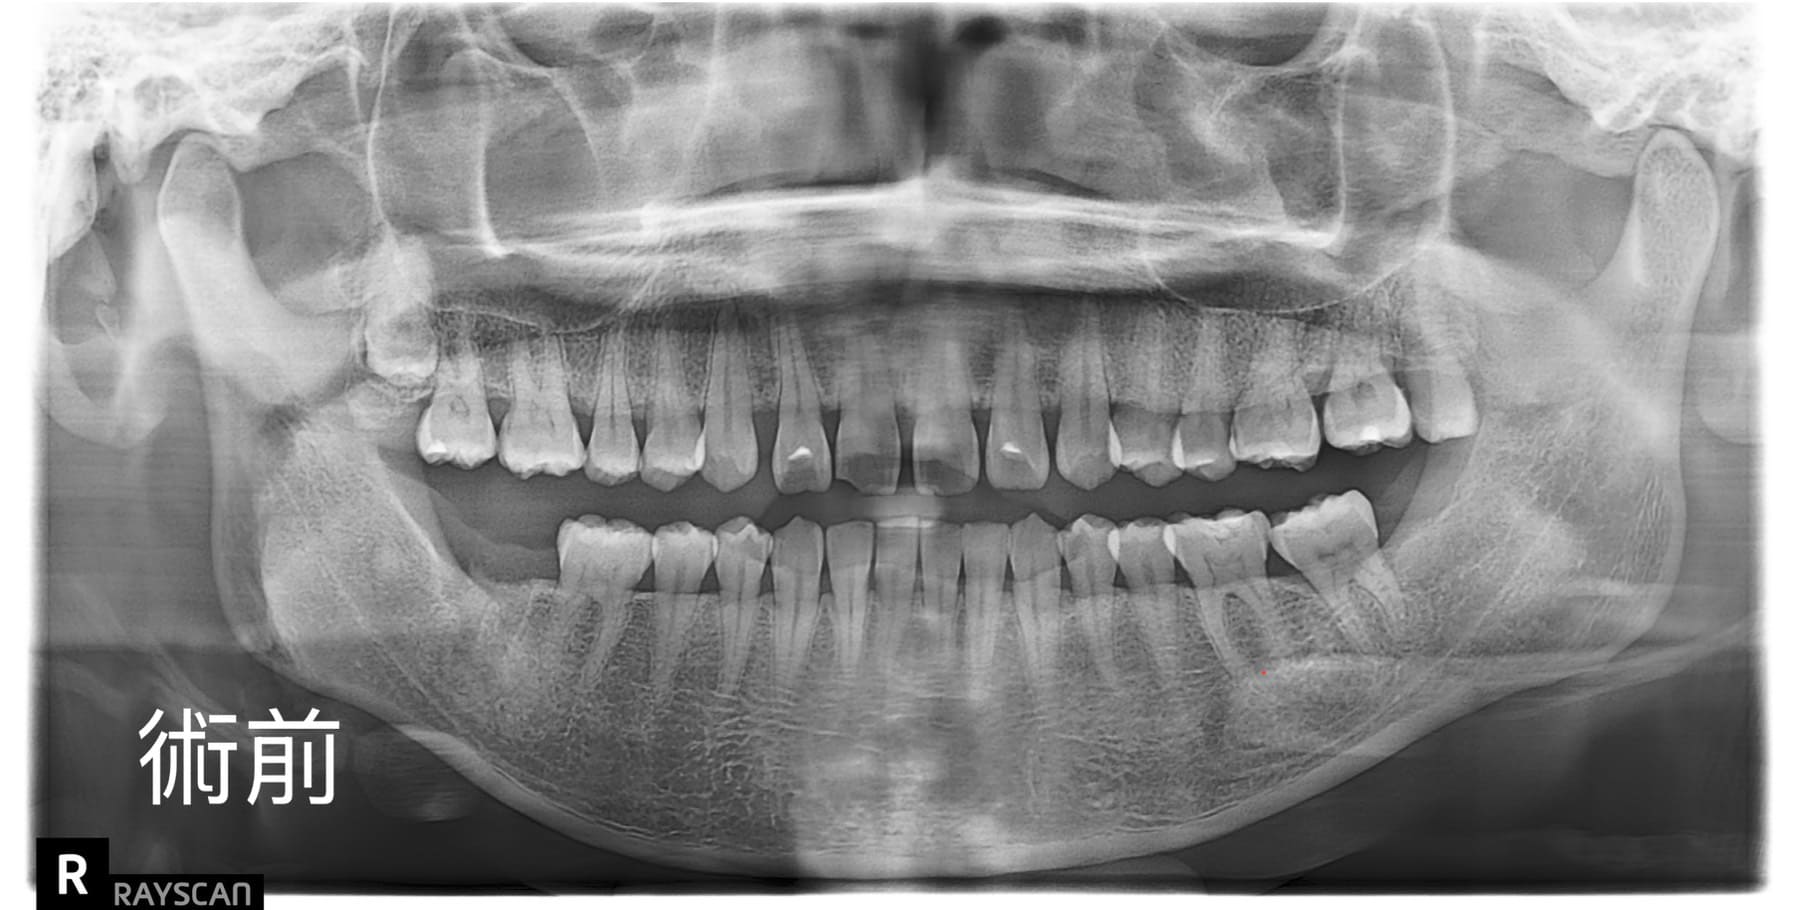

適采牙醫診所數位植牙案例

.jpg)